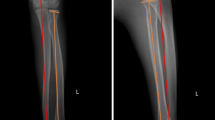

The mean follow-up time was 33 months (range 6–102 months) in 28 children. The mean posterior angle of ulna during the operation was 21°. All postoperative incisions were healed in one stage. No delayed union or non-union was found at the osteotomy site. No loose or broken plate was found. Transcapitellar joint K-wire was used temporarily in 5 cases with unstable radial head reduction in surgical technique. In 2 of five cases, subluxation was observed within 2 weeks after the operation, and the patients were sent to the operating room for temporary fixation with K-wire of the radiocapitellar joint. Approximately 3–6 weeks after the operation, the anteroposterior and lateral X-ray results of the elbow joint were reviewed, the K-wire were removed at 3 weeks and the plaster cast were removed at 6 weeks. No K-wire breakage and pin tract infections was observed. The elbow joint functions of all children improved, especially the flexion and extension functions. The elbow flexion increased from 116° before the operation to 137° after the operation (P < 0.001). Forearm rotation function decreased. However, no statistical significance was noted (P > 0.05) (Table 2). Three children with radial nerve injury before operation were noted, and these patients underwent exploration and release during the operation. The finger extension function started to improve at 2–4 weeks and recovered completely at 3–4 months after the operation. X-ray results showed that the radial head was in place with no dislocation or subluxation and no delayed union or nonunion at the last follow-up. Typical cases are shown in Figs. 2, 3.

Typical case 1: A 3.5-year-old boy with left missed Monteggia fracture. (A) Bado I type, ulna bow sign is located in the middle of ulna (group A). (B) In operation, reverse angulation is 24°, and radial head reduction is observed. (C) No dislocation of the radial head is found after the osteotomy is healed and the internal fixation is removed. (D) The elbow joint function is good after operation, no loss of rotation function.

Typical case 2: An 8-year-old boy with right missed Monteggia fracture. (A) Bado type I, ulna bow sign is located at the distal end of ulna (group B). (B) Reverse angulation 12° during operation, radial head reduction. (C) At 5 months after operation, the radial head is in place, and the osteotomy end has completely healed. (D) At 1 year after operation, the radial head is in place. (E) The elbow joint function was good 4 years after operation.